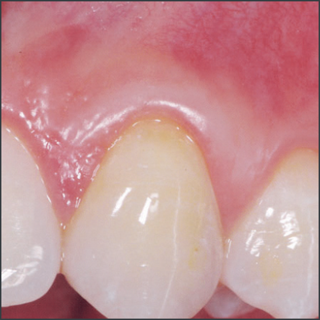

Before treatment with Straumann® Emdogain®.

Courtesy of Prof. Carlos Nemcovsky